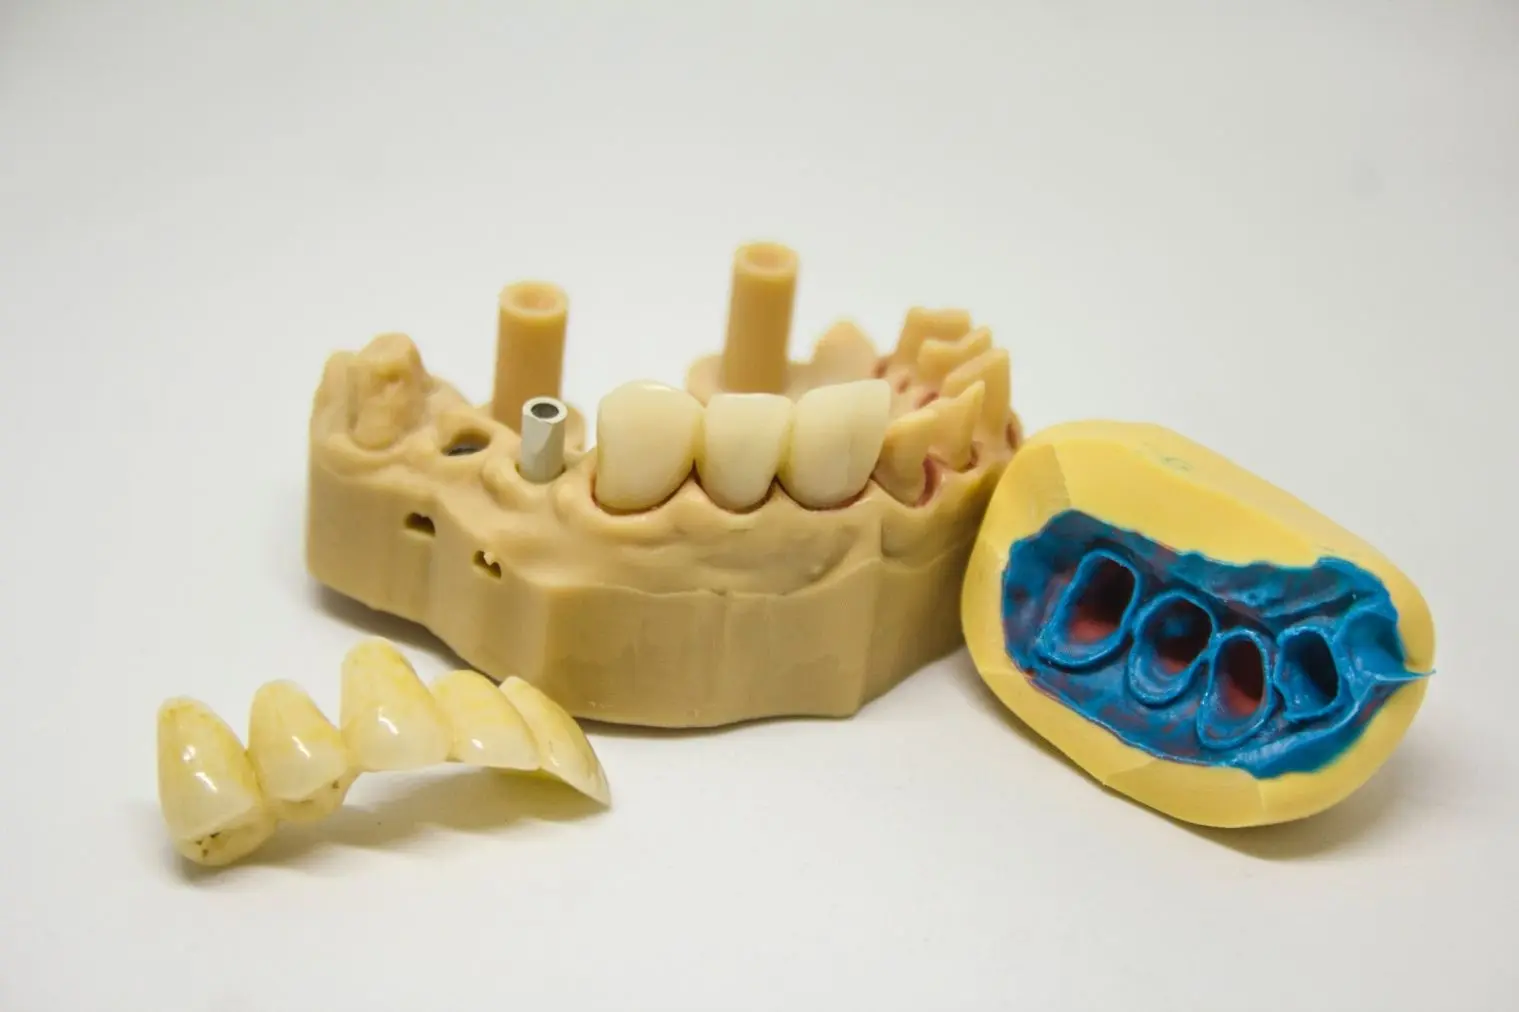

IMPLANT

Implant parçaların ağızdaki pozisyonlar ve açılarındaki farklılıklar her implant abutment parçası için kişiye özel üretim yapılmasını gerektirmektedir. Magical Touch hem müşterilerinden gelen hazır parçaların kişiselleştirilmesi, hem de kişiye özel yaptığı tasarımları üreterek bu alandaki ihtiyacı en iyi şekilde karşılamaktadır.

İmplant tekniğinde uygulamalar birbirinden farklı nitelikte teknikler çerçevesinde yerine getirilebilmektedir. Toronto imlant üstü porselen uygulaması işlemi bunlardan biridir. Kaliteli diş laboratuvarı alanlarında üretimi yapılan dişler, ilgili tedavi metodu kapsamında implant üstü protez olarak kullanılabilmektedir.

ALL ON FOUR

Alt çene siniri , üst çenede ise maksiller sinüsler bu bölgelere implant yapılmasına engel olurlar. Buralara implant yapmak için ileri cerrrahi tekniklere ihtiyaç duyulur ki bu da hasta için yaklaşık 1 yıllık tedavi süresi ve yüksek maliyet demektir. All on four tekniğinde ise bu anatomik engellerin önünde hastaya sabit bir protez yapılma şansını verir.

ALL ON SIX

All on six tekniğinde alt çene siniri , üst çenede ise maksiller sinüsler bu bölgelere implant yapılmasına engel olmasının önüne geçer ve yaklaşık 1 yıllık tedavi süresi ve yüksek maliyetin önüne geçer. Hastalar için anatomik bilgimiz ve uzmanlığımız ile en iyi hizmetlerimizi sunmaktayız.